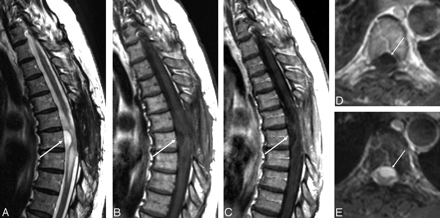

The images (Fig 1) demonstrated an extramedullary lesion, posteriorly located and extending from T5–T6 to T8, compressing the spinal cord anteriorly. The axial images (Fig 2) were the most useful in demonstrating the extramedullary location. The lesion was well defined, with some septa inside. It was essentially isointense with the CSF on all pulse sequences. The adjacent spinal cord was abnormal on T2-weighted sequences with a hyperintense appearance (T5–T6) (Fig 1A,-B). After gadolinium injection (Fig 1C,-D), there was no enhancement of the cystic extramedullary lesion. No enhancement was seen within the spinal cord, but the cord surface was covered by a rich vascular, enhancing network, probably because of the compression of the venous plexus system. No other abnormalities were found within the brain or in the spinal cord. The final preoperative diagnosis was arachnoid cyst with spinal cord compression.

Axial T2-weighted images at different thoracic levels (A and B) better illustrate the extramedullary location of the lesion (arrow) and its posterior, lateral right position.

Regression of the symptoms, primarily the gait impairment, occurred after surgery. The immediate postoperative MR imaging (Fig 5) showed total resection of the retromedullary cyst. Surprisingly, a new intradural extramedullary cyst was found at the level of T6, anteriorly located but still compressing the spinal cord. This new cyst showed the same characteristics of the previous one. There was persistent abnormal signal intensity within the spinal cord on T2-weighted images (Fig 5A).

Postoperative MR imaging. Sagittal T2- (A) and T1-weighted images before (B) and after (C) gadolinium injection; axial T1- (D) and T2-weighted (E) images. A ventral intradural extramedullary T6 lesion is found, presenting the same features as the previously removed lesion.